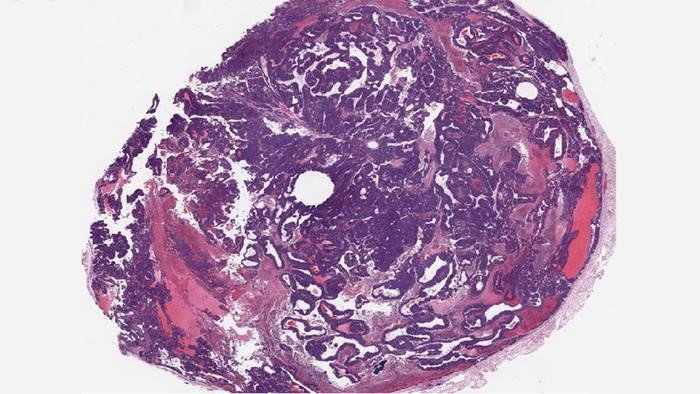

Предыдущие исследования показали, что отключение BPTF замедляет рост раковых клеток молочной железы, но не останавливает формирование опухолей. Поэтому фармацевтические компании не возлагали надежд на этот белок. Однако Чикконе и его коллеги увидели в нём потенциал. Они скрестили классическую модель рака молочной железы с мышью, у которой был отключён BPTF. Было обнаружено, что опухоли у гибридных мышей оставались ER+ на протяжении всего периода развития.

«Не существует модели, которая поддерживала бы гормонозависимый рак на протяжении всего цикла развития опухоли. При лечении тамоксифеном, одним из наиболее распространенных гормональных препаратов для лечения ER+ рака молочной железы, опухоли реагировали на лечение и не росли. Именно тогда мы поняли, что нащупали верный путь», — сказал Чикконе.

[Фото: dos Santos lab/CSHL]